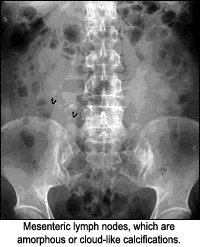

- cloud-like.

Rim-like appearance can be described as a wall of calcification surrounding a hollow structure, as in a renal cyst. Track-like or linear calcification indicates a tubular structure, as in the walls of the ureters or arterial walls. Lamellar calcification is formed in the lumen of a hollow structure, as in renal stones or stones in the gallbladder. Cloud-like calcifications are formed in a solid organ or tumor, such as a leiomyomas of the uterus or calcifications in the pancreas. Once the appearance of the calcification is apparent, the next step is to consider what anatomical structure is in that location. I am assuming one has ruled out the possibility of an artifact before considering a calcification as such.

- lymph nodes (calcified mesenteric lymph nodes are common)

Renal calculi sometimes can be confused with mesenteric lymph node calcification or phleboliths, depending on location. The kidney calculi are frequently found in the lower end of the ureter, where it turns to enter the bladder. Other locations are the uretero-pelvic junction and where the ureter crosses the iliac vessels in the pelvis. An estimated 80 percent of all kidney and ureteral stones are visible on plain films. Unfortunately, this is technique-dependent.